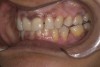

Fig 4. Centric wax record with Lucia jig.

Figure 4

A difference between MIP and CR was identified through a gentle maneuver using a Lucia jig that guided the mandible into CR (Figure 4). The upper cast was then mounted on a semi-adjustable articulator with a facebow record and the lower cast with a centric record. Articulator mounting showed that when the condyles were in CR, the teeth did not occlude in MIP. On opening the centric lock on the articulator and allowing the teeth to touch in MIP, the authors found a lack of space available to restore the palatal surfaces of the maxillary anteriors. Thus, a decision was made to keep the condylar rods in CR on the articulator, which would create some space in the anterior zone to restore the palatal surfaces of the maxillary anteriors.